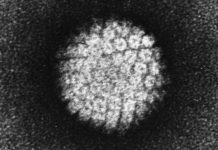

Anteriormente, los científicos en Alemania descubrieron que la transmisión del VIH está relacionada con la presencia de un amiloide fibrilar en el semen. Este fibrilar – una pequeña estructura, con carga positiva derivada de una proteína más grande – promueve la infección por VIH, ayudando a los virus encuentran y se unen a su objetivo: T CD4 células blancas de la sangre. En la edición de mañana de Cell Host & Microbe, los investigadores en el laboratorio de Warner C. Greene, MD, PhD, director de investigación de virología y la inmunología en Gladstone, describe un segundo tipo de fibrillas, que también tiene esta capacidad.

En experimentos de laboratorio sobre muestras de semen humano, se identificó un segundo grupo de fibrillas -derivados de las grandes proteínas llamadas semenogelins – que mejoran la infección por el VIH así como SEVIhace. La eliminación de estos y otros componentes de carga positiva del semen disminuye la capacidad del VIHpara infectar las células T CD4 de sangre blancas. Lo que confirma el papel de estas fibrillas en la promoción dela infección por

«Nuestros experimentos sugieren que las fibrillas de derivados de semenogelins – el principal componente delsemen – son esenciales para la mejora de la infección por VIH en el semen», dijo Roan. «Pero estamos intrigados por su función natural, biológica y el hecho de que estas fibrillas se encuentran en los órganos reproductivos masculinos podría apuntar a un papel evolutivo en el fomento de la fertilización -.. Algo que estamos estudiando»